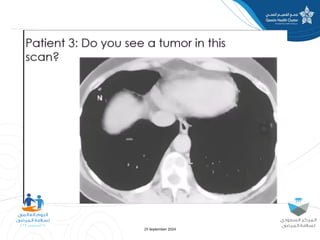

The document discusses diagnostic errors, particularly focusing on cognitive biases and their impact on decision-making in healthcare. Dr. Asmaa Fayez emphasizes the importance of recognizing and mitigating these biases to avoid human errors that can lead to serious incidents. The presentation highlights the urgent need for timely interventions in the context of patient safety.